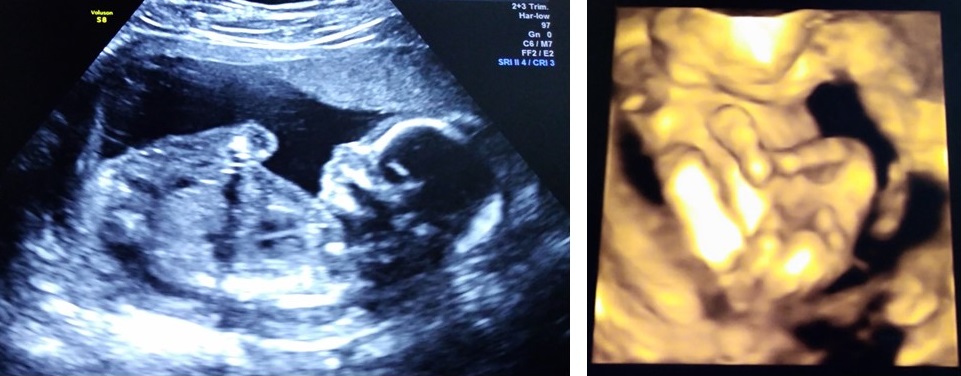

On the 13th August we enjoyed the treat of another ultrasound and 3D scan – baby is now getting bigger….baby is very active with a strong heartbeat…..all the bits are there and his organs; brain, heart, liver, kidneys etc are developing and show no health problems.

2018.08.13 hello Peanut 🙂 – look how big you’ve grown